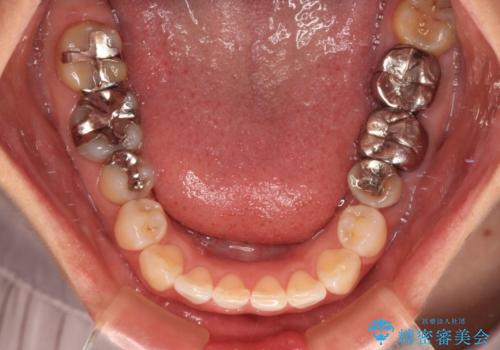

- 上下前歯のデコボコを気にして来院された患者様です。

カウンセリングにて詳しく話を聞いたところ、一番気になっているのは下顎前歯の叢生であり、上顎犬歯はあまり気になっていないとのことでした。

矯正治療は、歯の後戻りを抑制するために、治療終了後も保定装置をしっかりと使用していただくことが必須であるため、気になっている下顎だけを整えることで、その負担を半減できると考え、下顎のみの部分矯正として治療を行うこととしました。

当院では治療前の歯列が整っていない限り、下顎前歯の舌側をワイヤーで固定するようにしています。下顎のみの部分矯正としたことで、マウスピース保定の負担を軽減することができました。